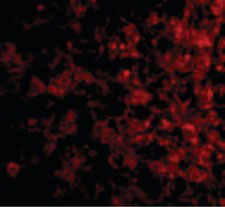

Immunofluorescence of TSLP Receptor in Human Liver cells with TSLP Receptor antibody at 20 ug/ml.